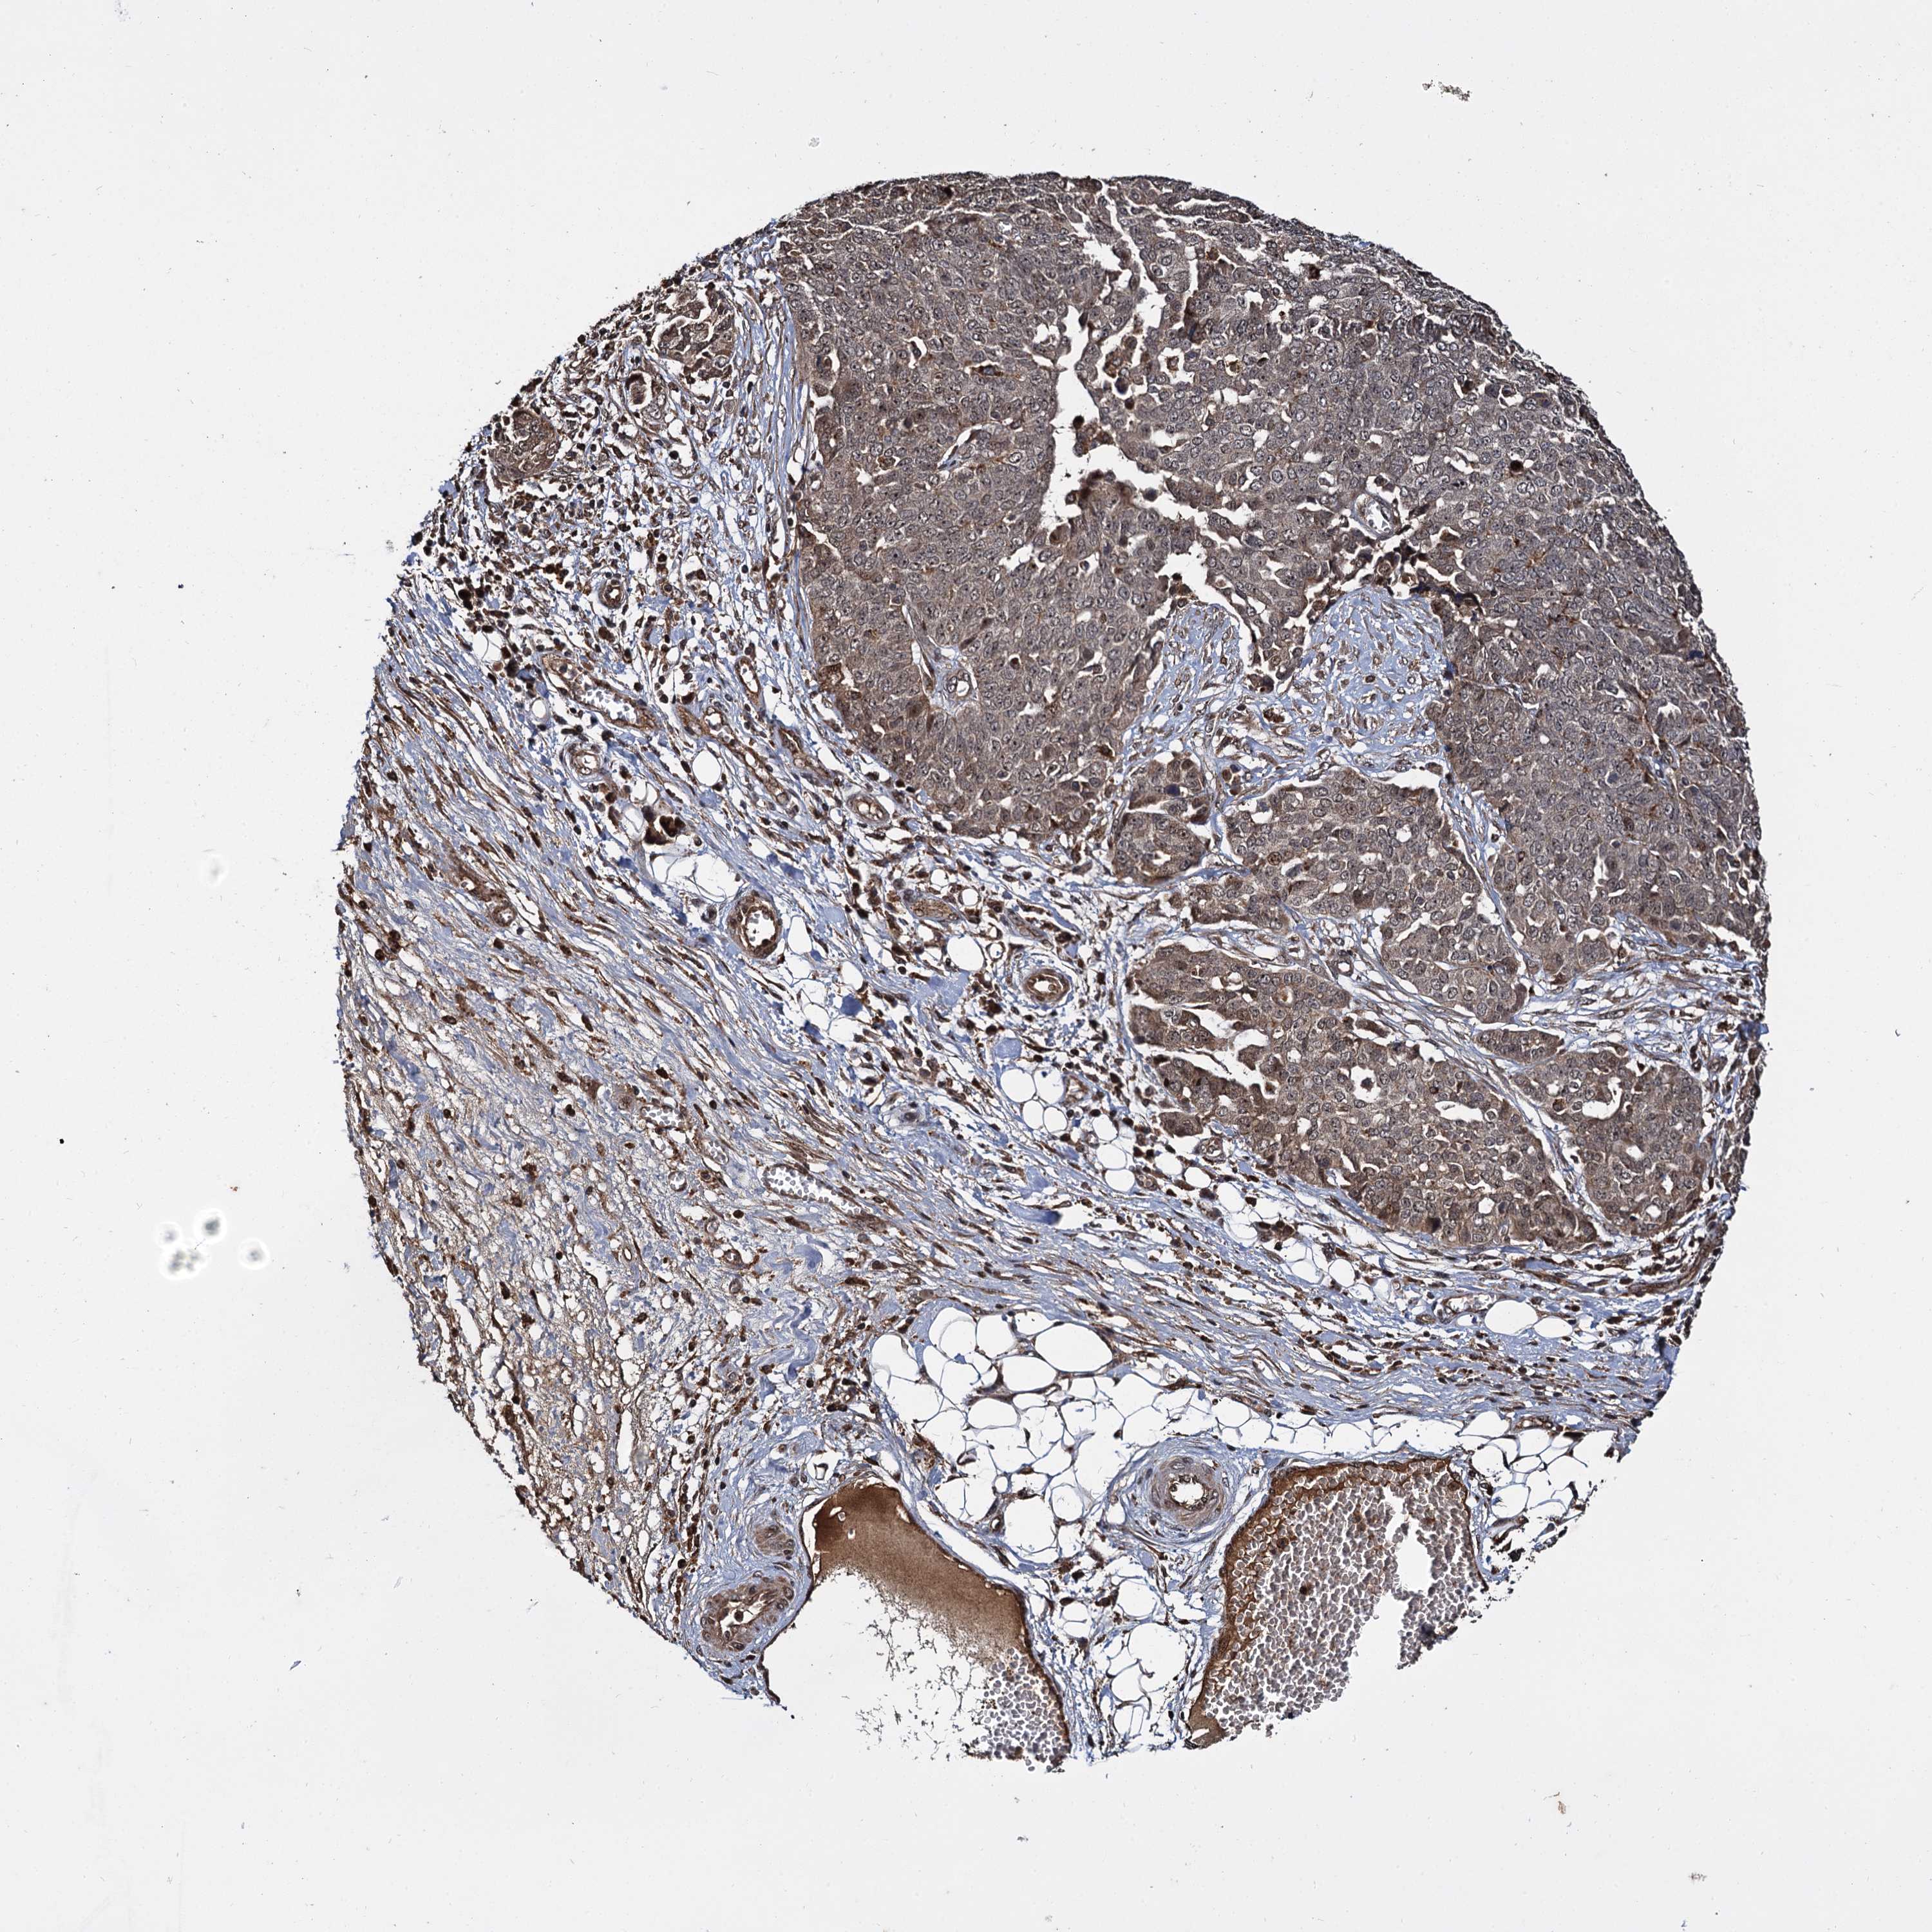

OVARIAN CANCER - Protein expressioni

A mouse-over function shows sample information and annotation data. Click on an image to view it in a full screen mode. Samples can be filtered based on level of antibody staining by selecting one or several of the following categories: high, medium, low and not detected. The assay and annotation is described here.

Note that samples used for immunohistochemistry by the Human Protein Atlas do not correspond to samples in the TCGA dataset.

Antibody stainingi

Antibody staining in the annotated cell types in the current human tissue is reported as not detected, low, medium, or high, based on conventional immunohistochemistry profiling in selected tissues. This score is based on the combination of the staining intensity and fraction of stained cells.

Each image is clickable and will lead to virtual microscopy that enables deeper exploration of all samples and also displays staining intensity scores, fraction scores and subcellular localization as well as patient and tissue information for each sample.

Antibody HPA039392

Antibody HPA040503

Cystadenocarcinoma, serous, NOS

Carcinoma, endometroid

Cystadenocarcinoma, mucinous, NOS

Carcinoma, NOS